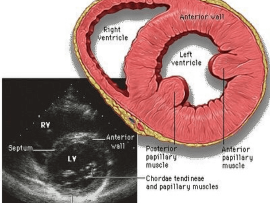

Lee masParasternal short axis view. Papillary muscle level. The importance is ; 1) can assess the LV function 2)Ischemia “RWMAs” 3)VSD 4)Flattened D-shaped septum in Pulmonary embolism 5)LV wall thickness 6)Papillary..